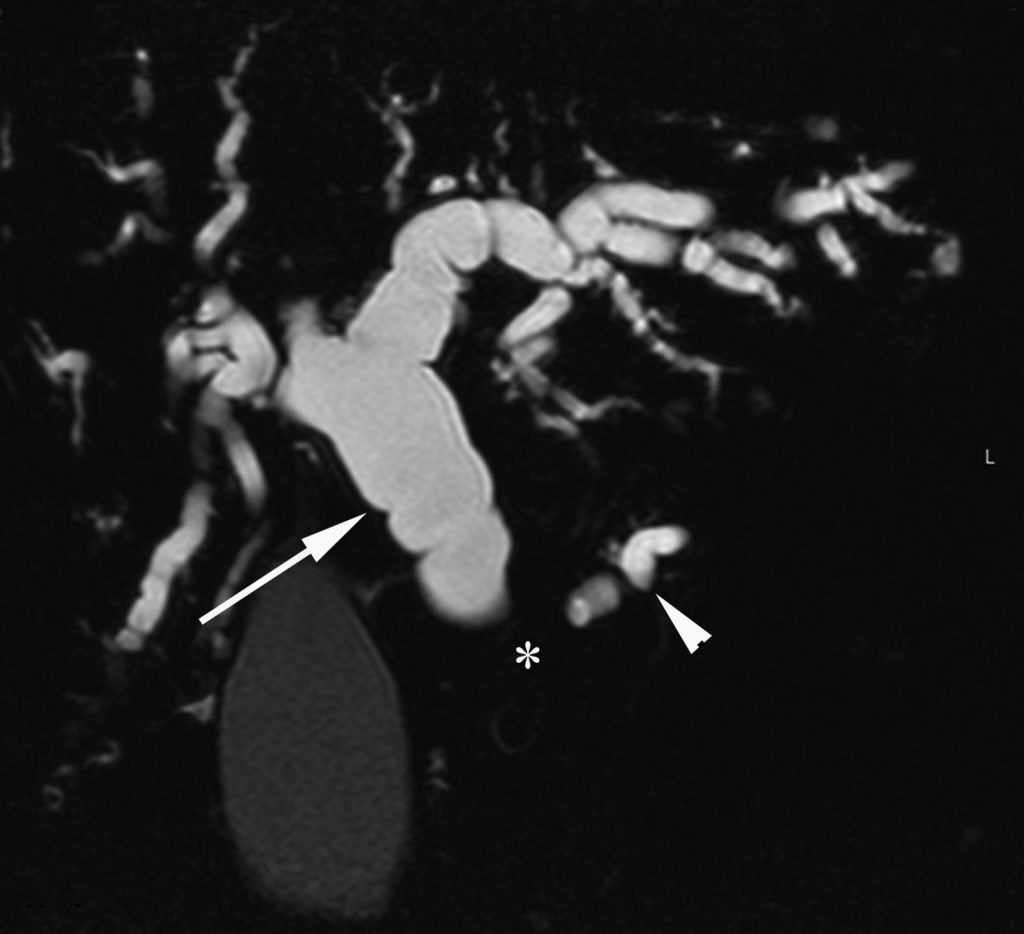

De même, en IRM, la tumeur est en léger hyposignal par rapport à la glande sur les séquences en pondération T1 avant et après injection de gadolinium.

Du fait de la difficulté de voir directement la tumeur, les signes indirects sont donc très importants à rechercher pour ne pas méconnaître la lésion, facilement visibles en échographie, au scanner (figure 18.3) ou en IRM (figure 18.4) :

- la dilatation du conduit pancréatique principal si la tumeur se situe sur le corps ou la queue du pancréas avec, dans ce cas, de possibles épisodes de pancréatite aiguë ;

- et/ou la dilatation des voies biliaires si la tumeur est développée dans la tête du pancréas. Dans ce cas, les examens d’imagerie montrent une dilatation des voies biliaires intra- et extrahépatiques et une grosse vésicule biliaire (hydrocholécyste). Il y a souvent un ictère associé sans fièvre (ictère nu).

Fig. 18.4. Exemple de cholangiopancréatographie IRM montrant une portion du conduit pancréatique dans l’isthme du pancréas qui apparaît dilaté (tête de flèche), ainsi qu’une dilatation importante de l’ensemble des voies biliaires intra- et extrahépatiques (flèche).

Cet aspect doit faire évoquer, de principe, la possibilité d’une tumeur de la tête du pancréas (invisible sur cette seule image de bili-IRM mais qui se situe en regard de l’astérisque).

Source : CERF, CNEBMN, 2022.